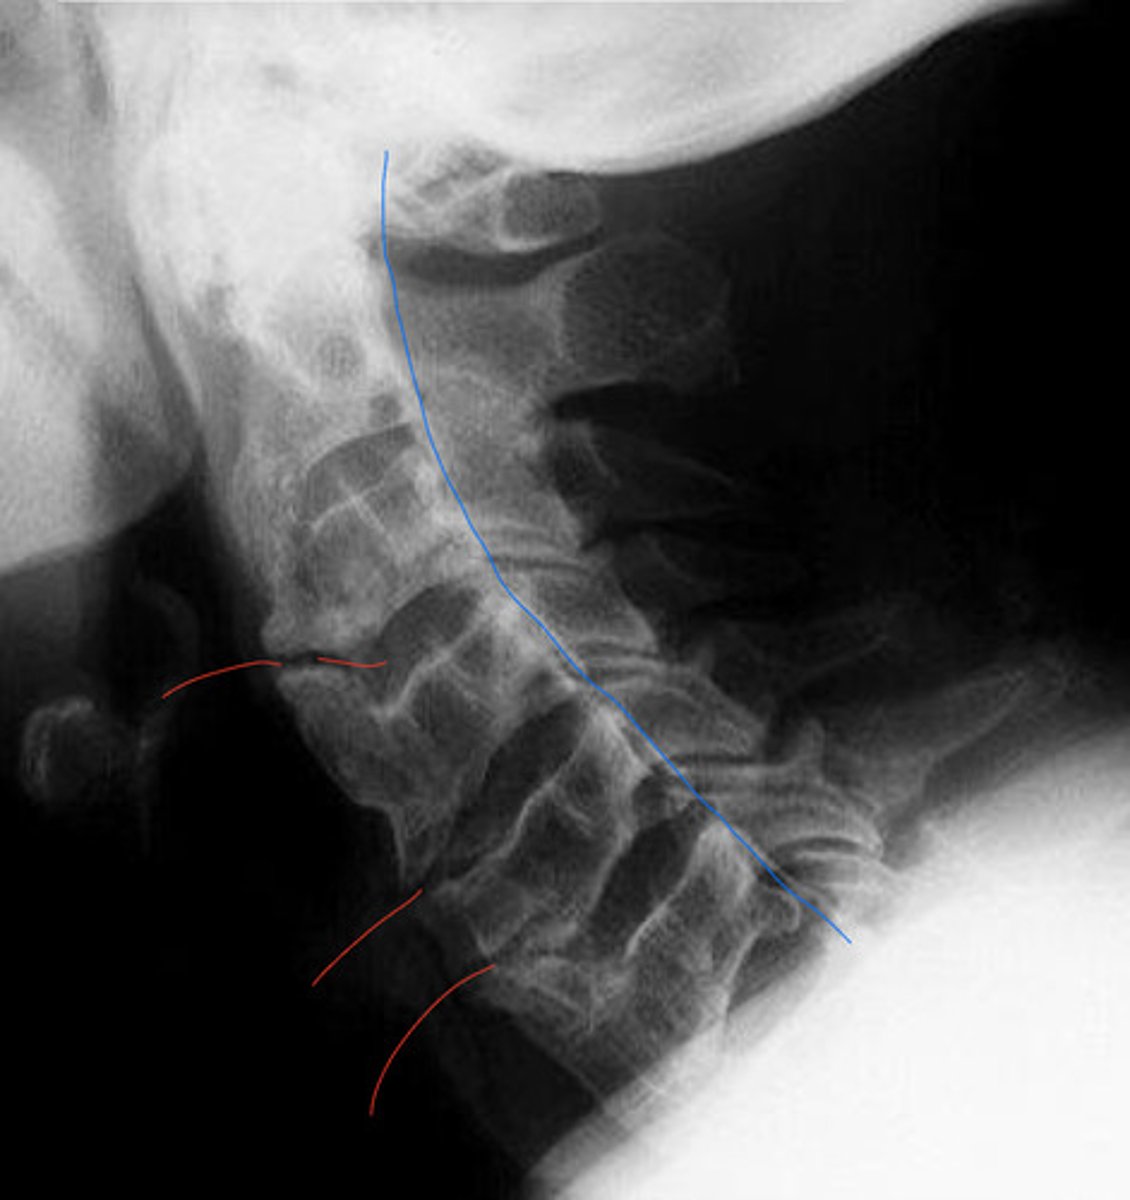

What is the blue?

What is the red?

DISH

What is the blue arrow pointing at?

Sclerosis of the posterior vertebral line

What is the pink?